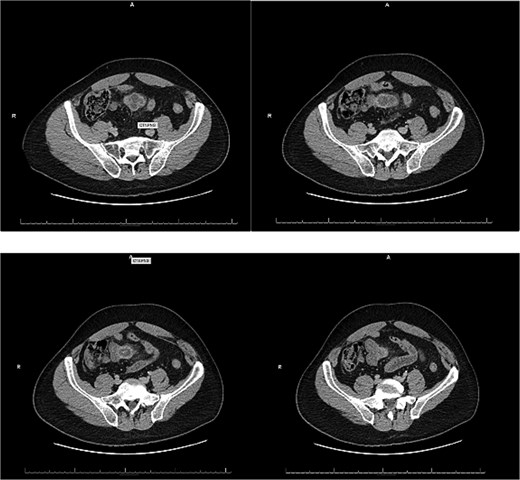

A 54-year-old male with a history of hyperlipidemia presented with several hours of worsening lower abdominal pain radiating to the right lower quadrant. He denied nausea, vomiting, diarrhea, or recent illnesses. On examination, he appeared uncomfortable, with a taut, non-distended abdomen, diffuse tenderness, and hypoactive bowel sounds. Laboratory studies revealed leukocytosis (WBC 22.37 K/μL), and an abdominal computed tomography (CT) showed a thick-walled, inflamed, blind-ending tubular structure in the midline pelvis with surrounding fat stranding and small bowel wall thickening, consistent with acute Meckel diverticulitis (Fig. 1). No bowel obstruction or fluid collection was identified. The patient was kept nothing by mouth (NPO), started on IV fluids and broad-spectrum antibiotics, and offered surgical intervention.